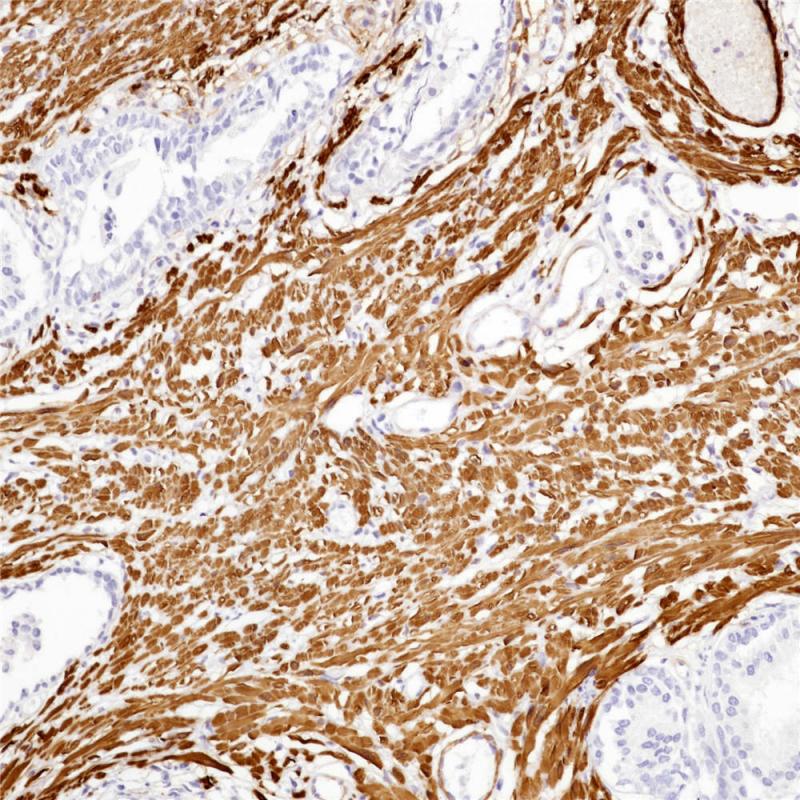

肝细胞肝癌AFP(BP6244)染色

甲胎蛋白(AFP)是一种存在于哺乳动物胎儿肝脏、卵黄囊和胃肠道的糖蛋白。AFP在成人正常细胞中表达较低,但在成人肝癌细胞中异常表达。肿瘤抑制基因p53和β-catenin都参与了AFP表达的调控。在正常的成年细胞中,p53结合到AFP基因的抑制区,从而阻断转录。p53和β-catenin的突变均与AFP的异常表达有关。研究表明,血清AFP水平升高是肝细胞癌的预测指标。AFP在成人肝组织中不表达,但在成人肝癌细胞中异常表达。AFP主要用于肝细胞癌的临床诊断。

阳性对照

肝细胞肝癌

亚细胞定位

细胞质